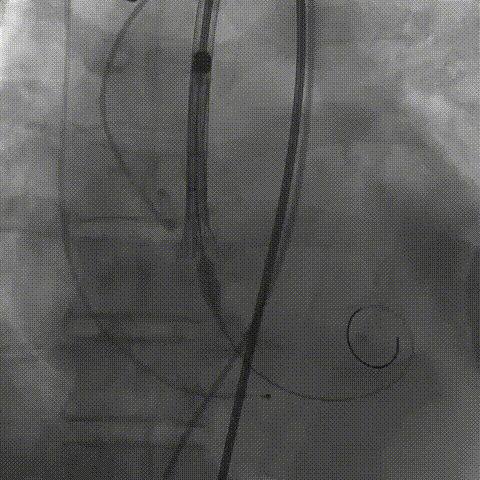

瓣膜(AV29)工作位正交体位造影位置良好,左冠显影正常

瓣膜(AV29)完全脱钩释放后23mm球囊充分后扩,冠脉灌注良好